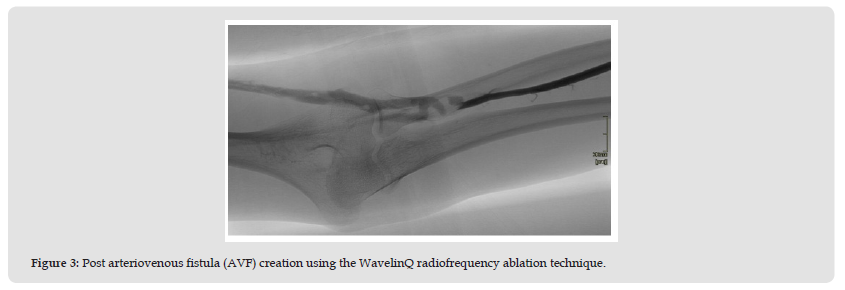

Procedure: The arteriovenous fistula (AVF) was created in September 2022 under regional anesthesia in a specialized operating room. Antibiotic prophylaxis with cephalosporin was administered prior to the incision. The patient was prepared and draped using sterile technique. A bedside ultrasound was performed to confirm the optimal vein location prior to the procedure. The patient was positioned supine and underwent a brachial plexus nerve block. The patient underwent a successful left forearm arteriovenous fistula (AVF) creation using the WavelinQ radiofrequency ablation technique. The procedure involved the following steps:

• A micropuncture needle was inserted into the distal left medial radial vein in an antegrade direction, followed by a standard wire. The needle was then replaced with a 4F sheath, and a venogram confirmed vein patency. A 0.18 wire was inserted through the sheath, and a 4F WavelinQ catheter was advanced over it.

• A similar procedure was performed on the distal radial artery, using a radial access needle and inserting a standard wire followed by a 4F sheath. An angiogram confirmed arterial patency, and a 0.18 wire and 4F WavelinQ catheter were inserted. A cocktail of (3000U heparin, 100 nitroglycerine) was injected.

• Under fluoroscopic guidance, a venogram was performed to assess the optimal site for AVF creation. The catheters were positioned approximately 4 cm distal to the elbow and connected to a radiofrequency generator. After removing the microwires, radiofrequency ablation was initiated at 60 watts for 0.7 seconds. Both catheters were then removed, and a post-procedural venogram confirmed successful AVF creation. The lateral brachial vein was embolized using a 10 mm concerto coil.

• Hemostasis was achieved through compression. The patient tolerated the procedure well and had no immediate complications. An excellent thrill was noted immediately post-procedure, indicating adequate blood flow through the fistula (Figures 2 & 3).